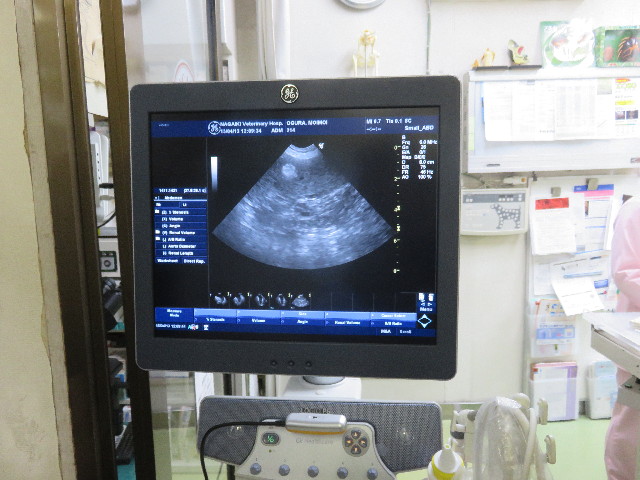

●2ケ月に度のエコー。

○膀胱きれい。

○前からある脾臓の結節10mm。悪いものではないので心配なし。脾臓の形きれい。

○前からある胆泥少量。問題なし。